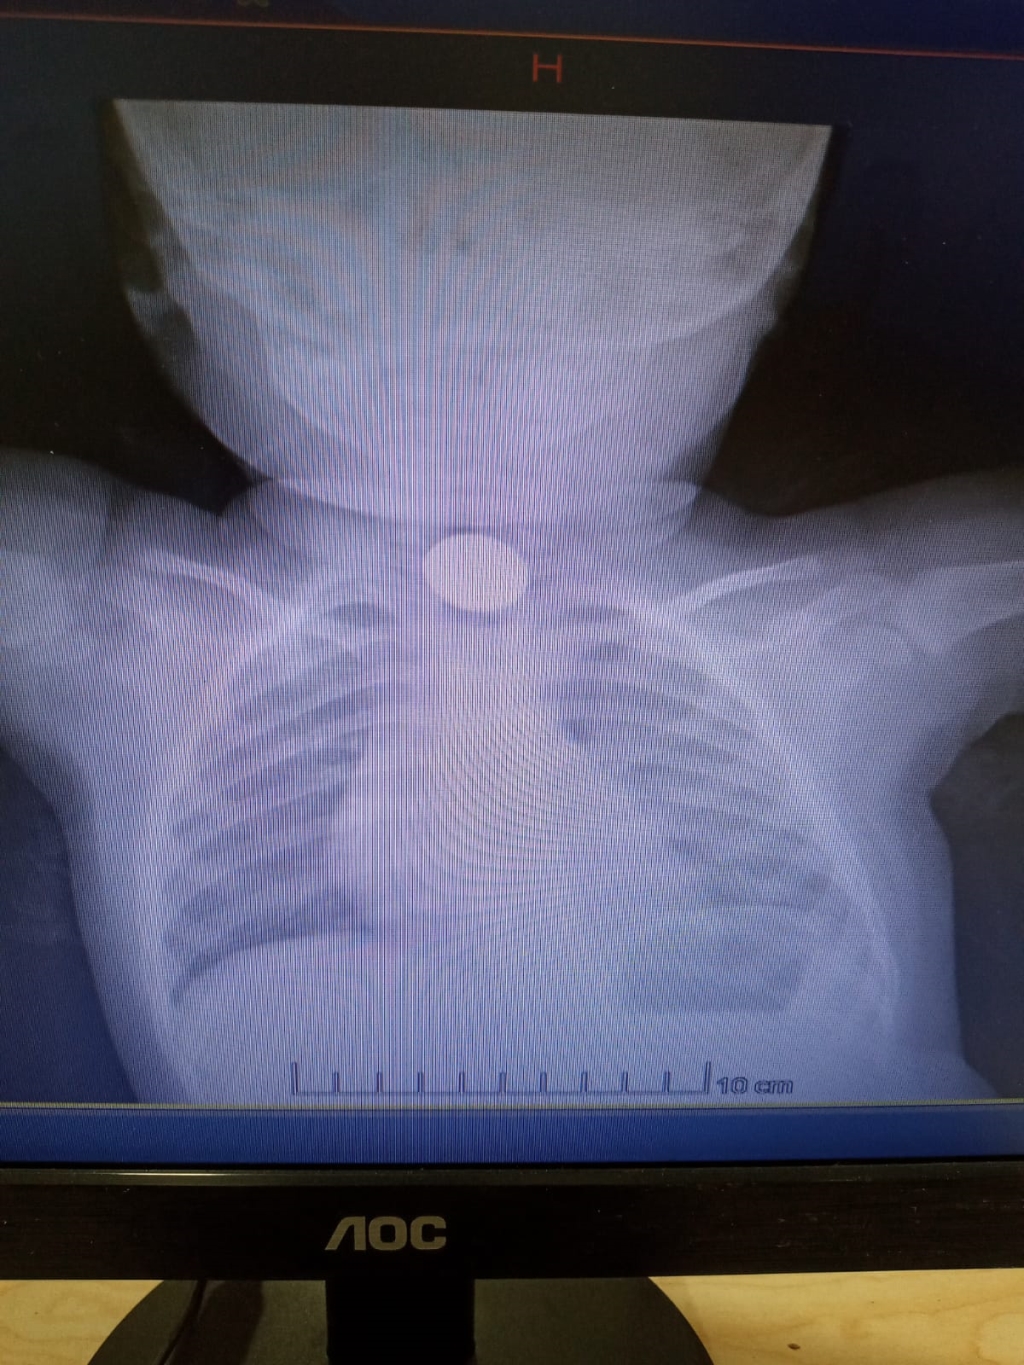

Ereğli'de evde oynarken madeni para yutan 1 yaşındaki D.D.Ç., ailesi tarafından özel hastaneye kaldırıldı. Doktorların müdahalede bulunduğu D.D.Ç.'nin çekilen röntgeninde 25 kuruşluk madeni para sindirim sistemi girişinde tespit edildi. Yapılan muayenede madeni paranın bebeğin yemek borusuna zarar vermediği anlaşıldı. Doktorların müdahalesi sırasında D.D.Ç., kusması sonucu madeni para kendiliğinden çıktı. Sağlık durumu iyi olan D.D.Ç., taburcu edildi.